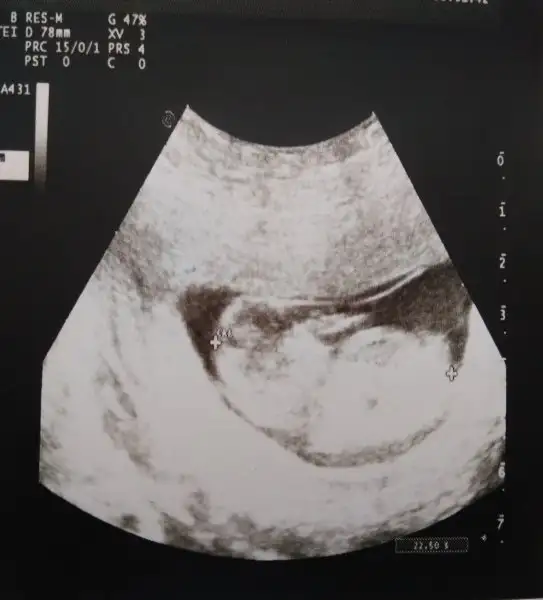

Bizim dünkü fotomuz bakar mısınız cinsiyeti belli mi 12+4 üz bu arada , Dr bı şey demedi cinsiyet için , heyecanla cevaplarinizi bekliyorum

Maşallah minise canım ultrason pek net değil tahmin edemiyorum o yüzden ama tahmin eden arkadaşlar bebis toplu duruyor kız bebek olabilir dicekler

Bütün teoriler kız diyor zaten bir tek doktorun ağzından duymadık o yüzden belki bir ihtimal kesinleşene kadar farklı söyleyen olur mu ki dedim acaba [/QUOTE]